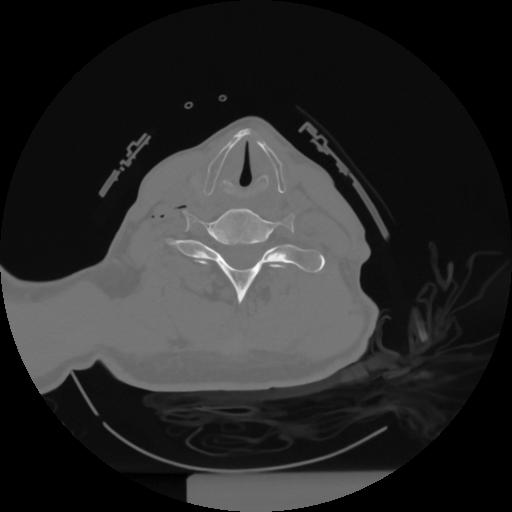

12 P.BLANDAS,,Vol,0.5,P.BLANDAS,,